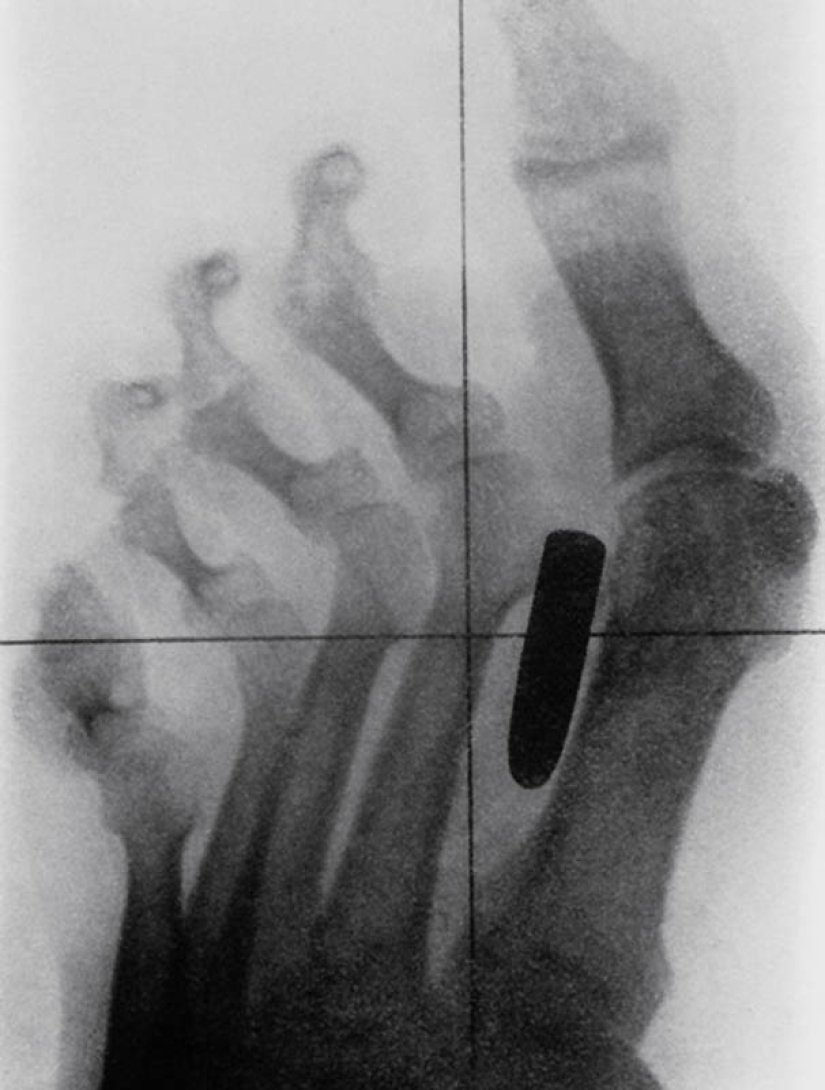

3. Ancient X-ray image of the foot of a soldier of the Anglo-Boer War (1899-1902) with a gunshot wound. The bullet lodged in the metatarsal bone between the thumb and second finger.